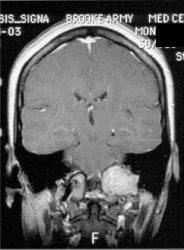

|

Glomus tumor: The octreotide exam was performed to assess for multifocality or metatstatic disease in this patient with a very large glomus tumor. Although the primary lesion is evident on whole body imaging (black arrow), SPECT images demonstrate the lesion more clearly (center). A coronal MR image of the lesion demonstrates marked enhancement following the IV administration of gadolinium due to the rich vascular nature of these lesions.. |